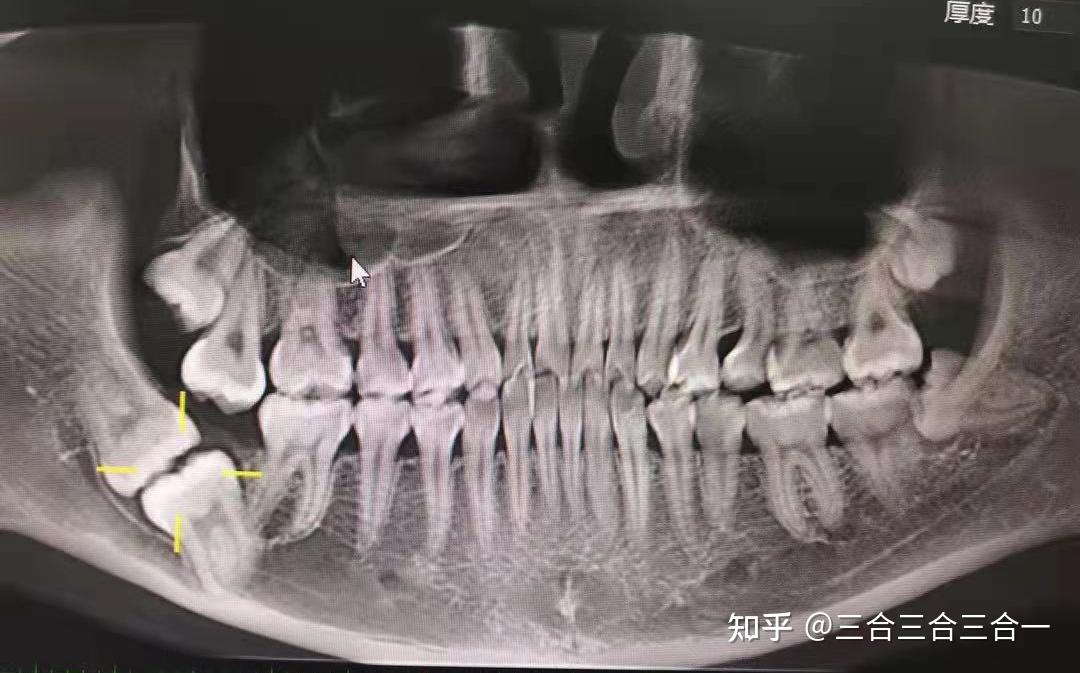

智齿x光图片正常

智齿x光图片正常,正常牙齿x光图片

右侧咀嚼时会有疼痛;医生建议拍个x光,查看右侧智齿情况

有朋友智齿这样长的吗

一颗神秘"失踪"的智齿